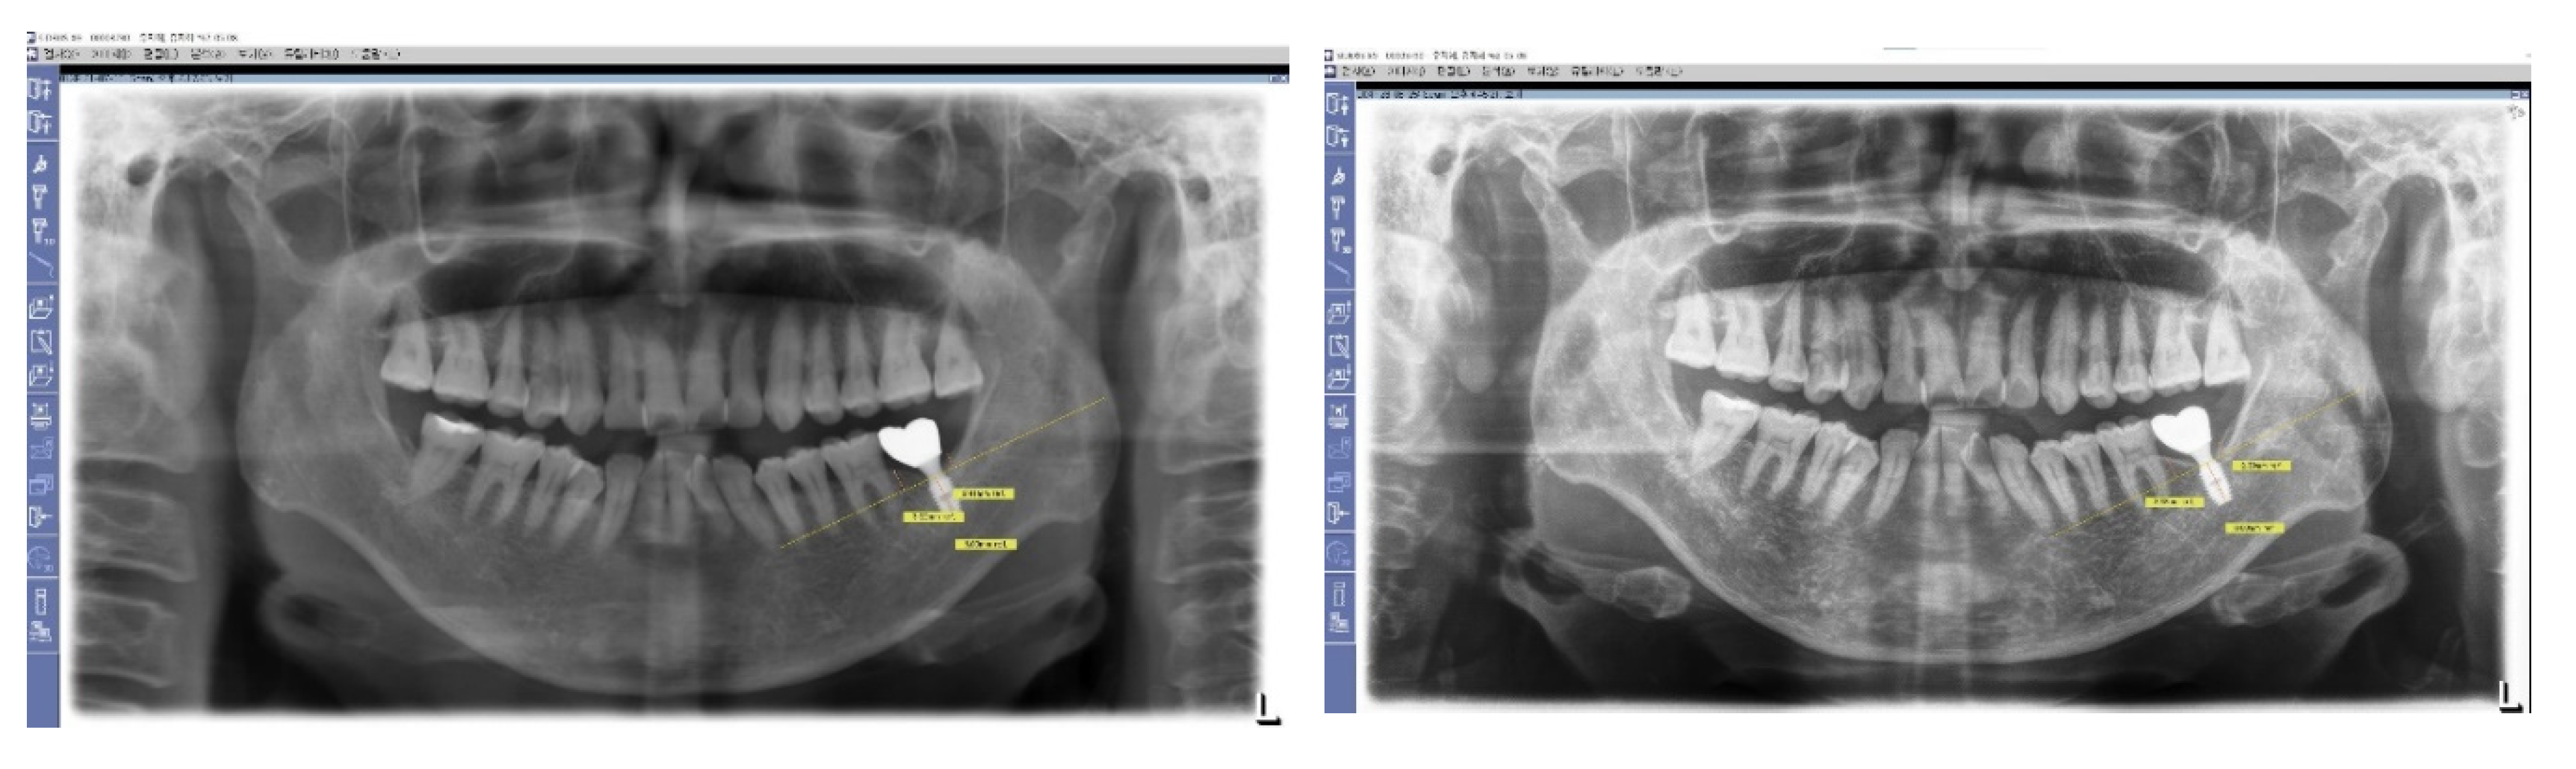

Figure 3 and Figure 4: Impact of Implant Placement Depth on Clinical Crown Shape

These figures demonstrate the effect of the depth of implant placement on the shape of the clinical crown. Figure 3 shows an equicrestal placement of a second molar implant, where insufficient vertical space necessitates a smaller diameter or an abrupt emergent profile for the clinical crown. In contrast, Figure 4 illustrates a subcrestal placement for a first molar implant, which provides sufficient vertical space allowing for the creation of a more natural-looking clinical crown with a gradual emerging profile.

Figure 3. Case Study of Epi-Crestal Placement of a Second Molar Implant. This figure illustrates a case where a second molar implant was placed epi-crestally, resulting in a smaller clinical crown size and an unnatural appearance due to an improper emergent profile compared to the adjacent natural molar. This outcome is attributed to the shallow depth of placement, which causes the transition part to be exposed supramucosally.

Figure 4. Comparative Case of Equicrestal vs. Subcrestal Implant Placement. This figure demonstrates the differences between equicrestal and subcrestal implant placements. For the implant in the position of the second molar, equicrestal placement results in a molar diameter reaching a short vertical distance, leading to an abrupt emergent profile with the transition part located supramucosally. In contrast, for the implant in the position of the first molar, subcrestal placement yields a more natural appearance, as it allows for a gradual emergence with the vertical distance matching the horizontal distance needed for diameter increase, and the transition part located submucosally.